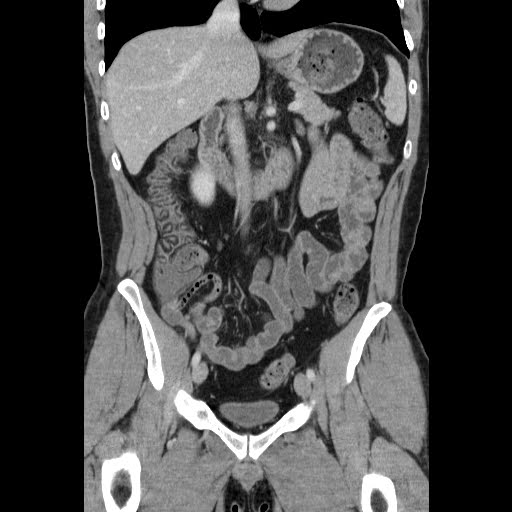

Fatty Liver

Fatty Liver,